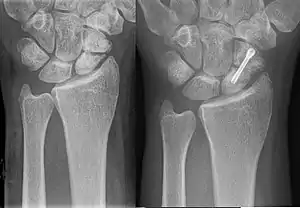

| An X-ray showing a fracture through the waist of the scaphoid | |

A subtle scaphoid fracture

A more obvious scaphoid fracture on a scaphoid view X ray

Radiolucency around a 12 days old scaphoid fracture that was initially barely visible.[12]